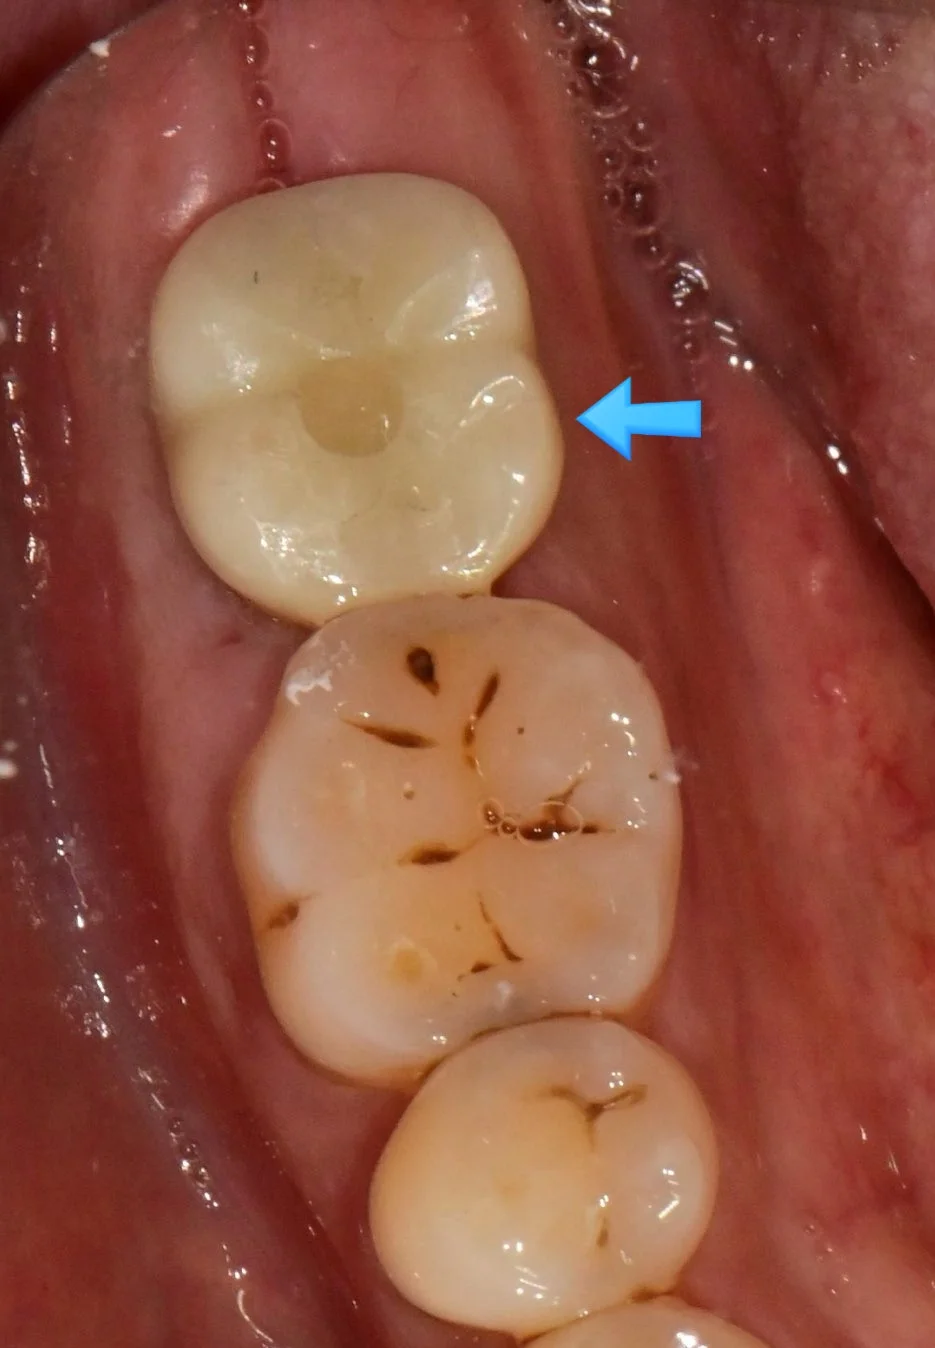

파노라마 X-ray — 정확한 위치에 임플란트가 식립된 것을 확인